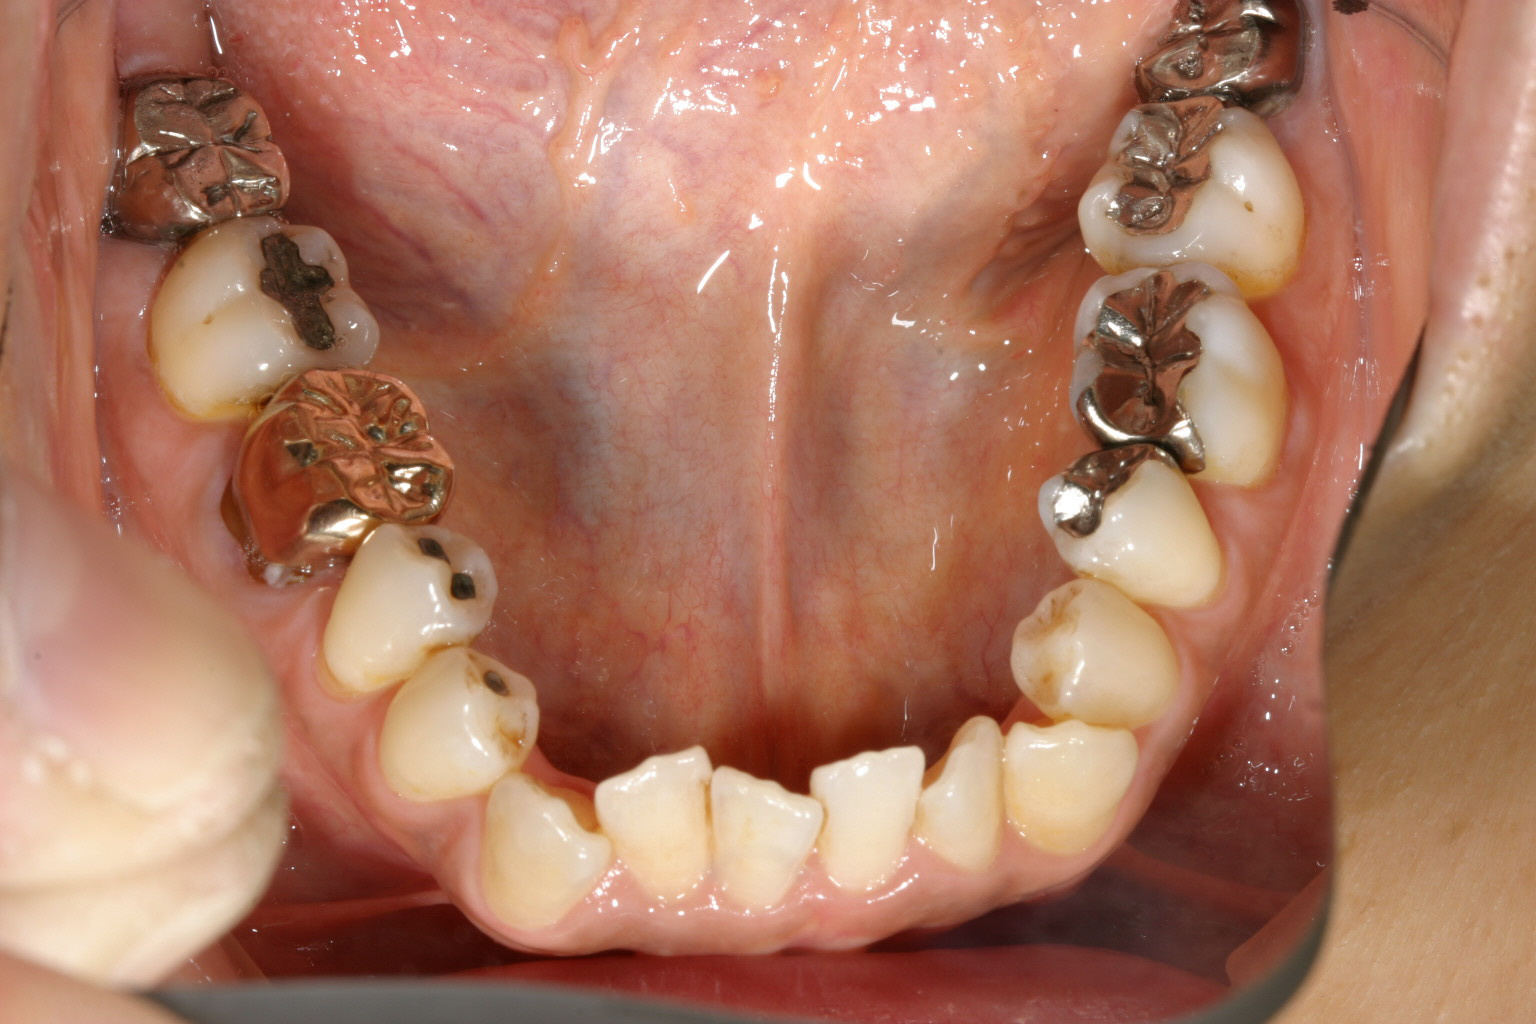

下顎も補綴物が多く又前歯部にガタガタが見受けられます。

凄い開咬ですね~ この症例にはマルチループワイヤーしかありません。